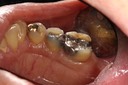

Alan Chinn #31 pre-op